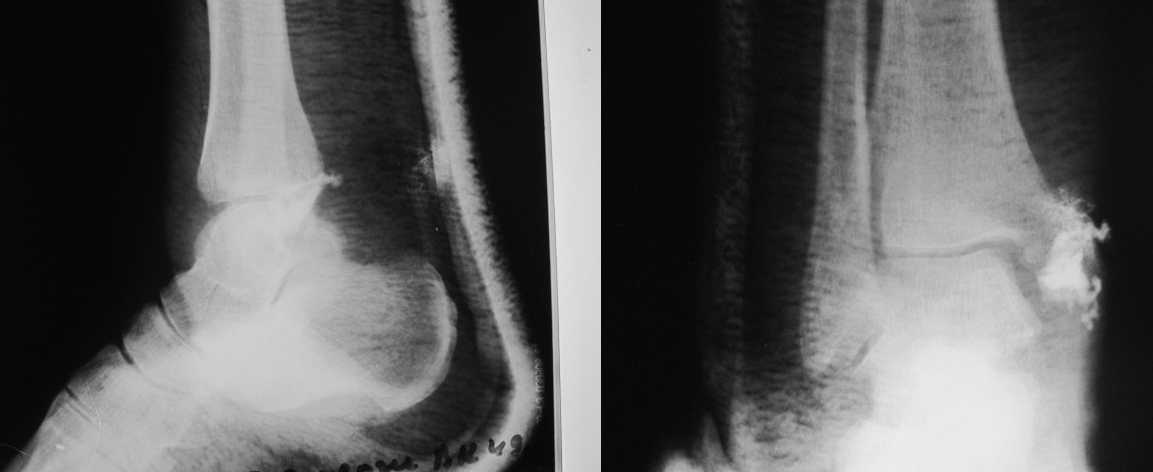

Прилагаю данные фистулогрфии. Основной вопрос, все же, лечить консервативно или оперативно? Если оперативно, то какой объем? А что если прийдеться резецировать всю медиальную лодыжку!?

Думаю, от нее будет мало толку, учитывая слишком маленький размер "очага", но после выходных сделаю! Больная сейчас на амбулаторном лечении.